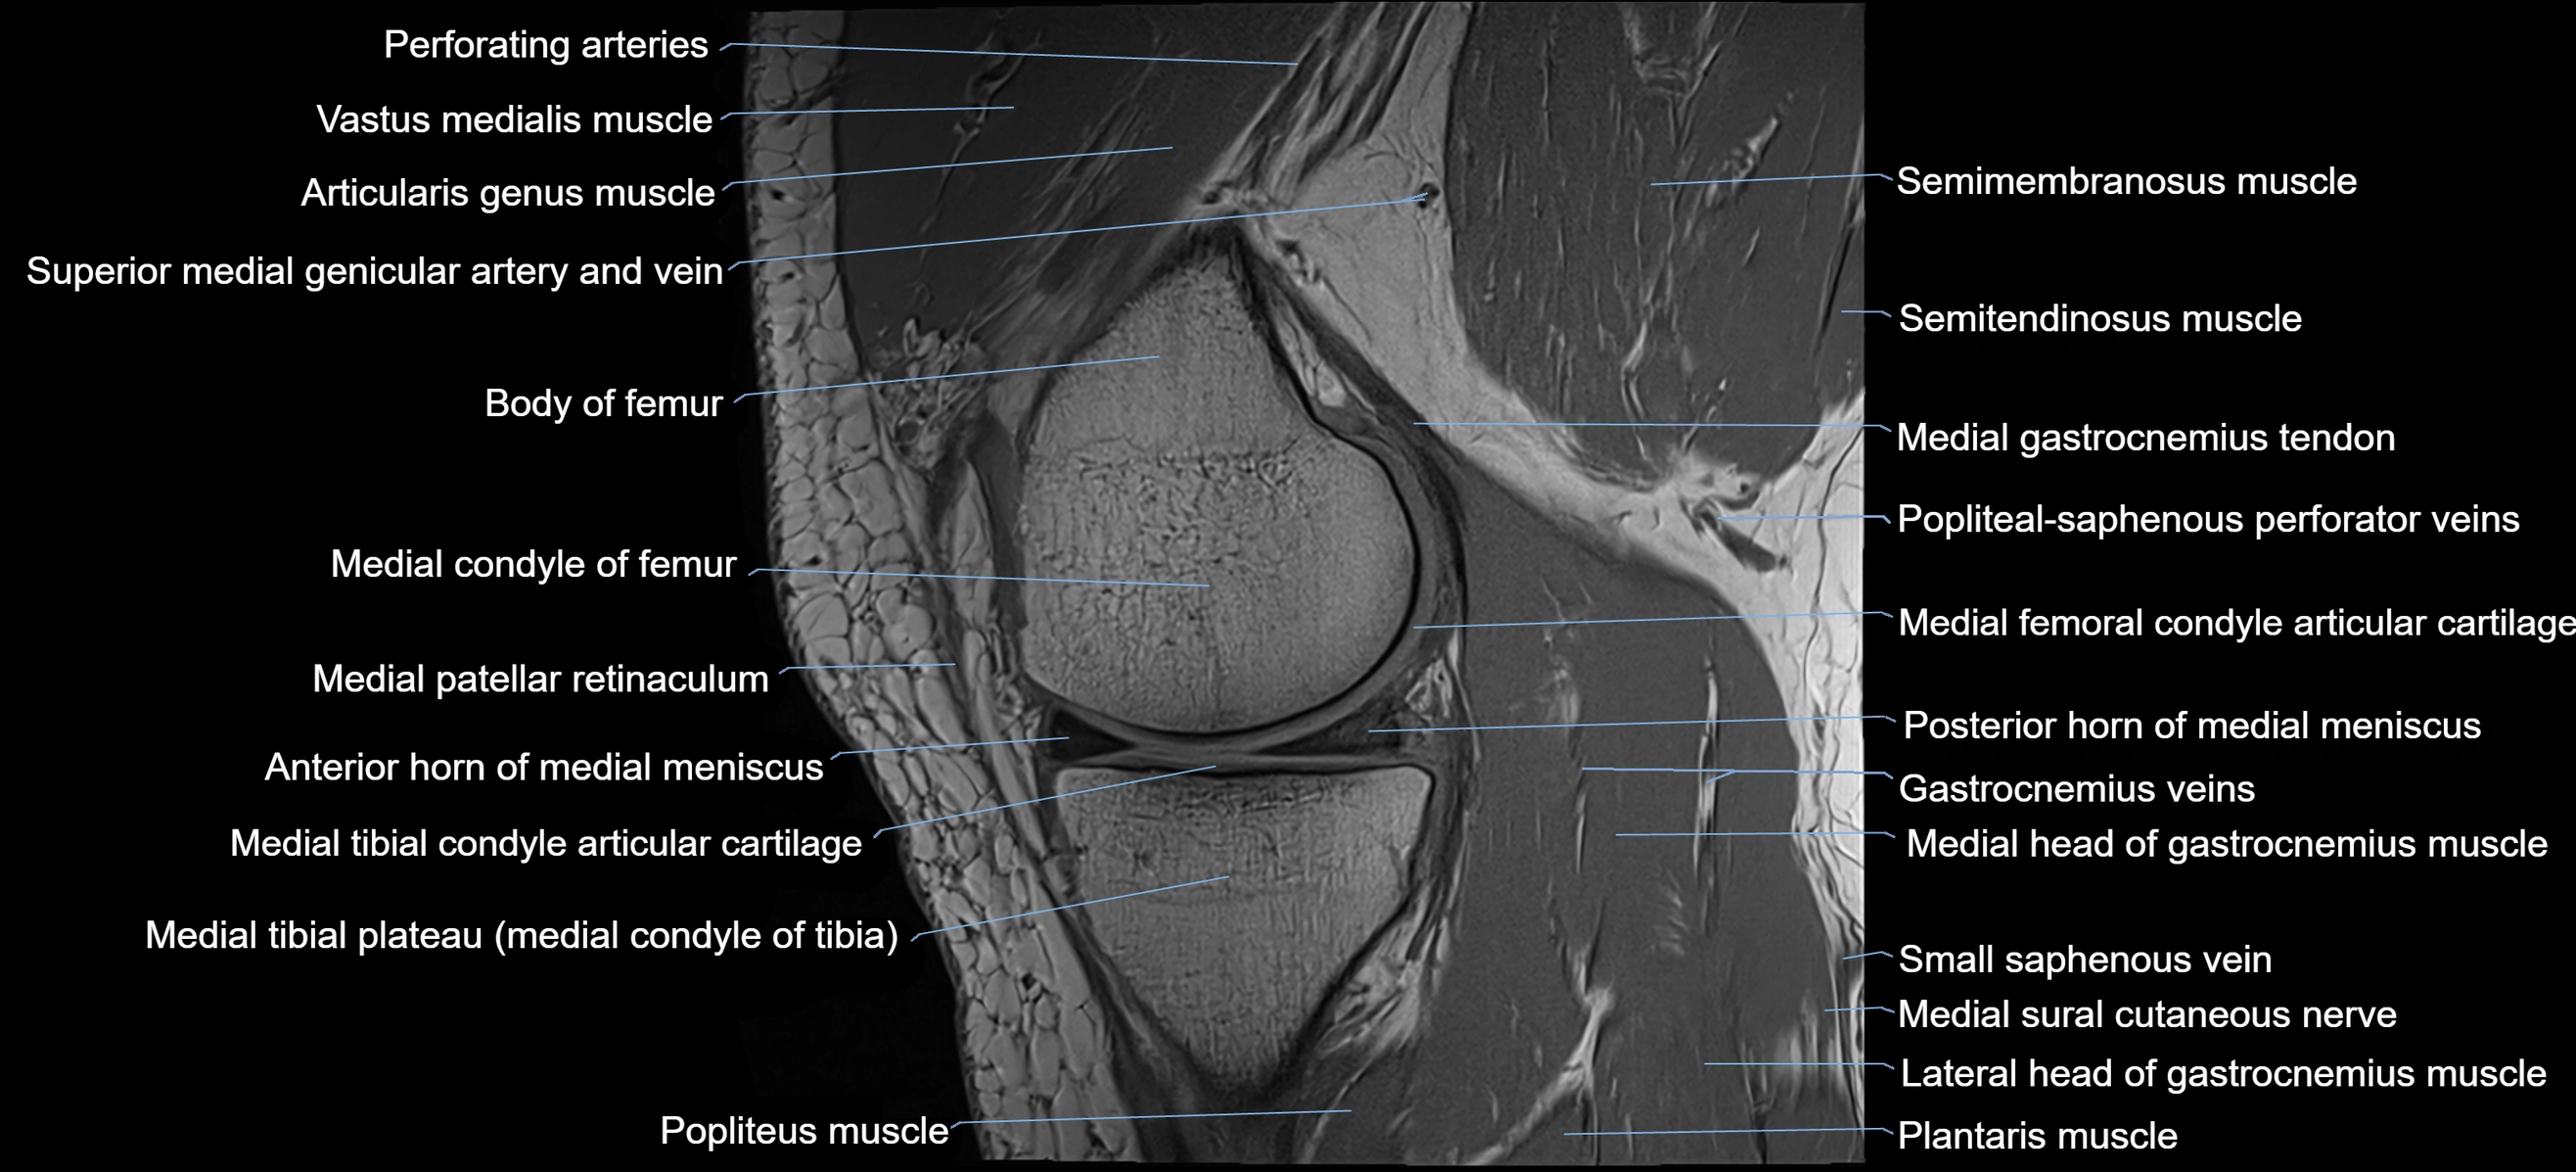

- Anterior horn of medial meniscus

- Anterior root of medial meniscus

- Body of medial meniscus

- Medial condyle of femur

- Medial condyle of tibia

- Medial gastrocnemius tendon

- Medial head of gastrocnemius muscle

- Medial meniscus

- Medial patellar retinaculum

- Medial tibial plateau

- Popliteus muscle

- Posterior horn of medial meniscus

- Semimembranosus muscle

- Semitendinosus muscle

- Small saphenous vein